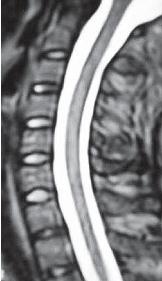

МРТ № 46

Возьмём за вариант нормы данный снимок МРТ № 46, на котором наблюдается нормально выраженный лордоз, высота межпозвонковых дисков, ширина позвоночного канала. Самое главное — отсутствие стеноза (сужения).

Спинной мозг: контуры ровные, чёткие, структура гомогенная (греч. homogees — однородный), расположен почти в центре позвоночного канала и имеет нормальную толщину. Участков его патологического расширения или сужения не наблюдается. Ликворные пути свободны, проходимы.